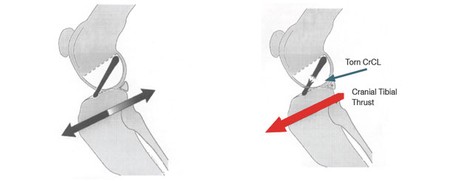

Secondo alcuni studi sulla biomeccanica dell’articolazione del ginocchio l’inclinazione del plateau tibiale rispetto all’asse della tibia stessa rappresenta un fattore determinante nella patogenesi delle rotture del legamento crociato craniale. Tale inclinazione è responsabile dell’intensità della “spinta tibiale craniale”, ossia di quella forza, generata dalla compressione tra femore e tibia durante il carico ponderale, che provoca la traslazione craniale della tibia, più l’inclinazione è elevata, maggiore sarebbe la spinta craniale della tibia.

La causa di rottura meno frequente è, invece, il trauma. Poiché, il legamento crociato craniale limita la rotazione interna della tibia sul femore, un danno a suo carico può avvenire quando l’animale in corsa effettua una svolta improvvisa di 180°. Un'altra causa traumatica di rottura è l'iperestensione del ginocchio che si può verificare, per esempio, quando il cane che corre blocca improvvisamente la tibia ( ad esempio perché entra in una buca con un piede ) mentre il resto del corpo continua la sua azione in avanti.

Qualunque sia la causa, dalla rottura del legamento crociato craniale deriva una instabilità persistente dell’articolazione del ginocchio, che determina infiammazione della capsula articolare e della membrana sinoviale, degenerazione della cartilagine articolare, produzione di osteofiti periarticolari e danni ai menischi sopratutto il menisco mediale.